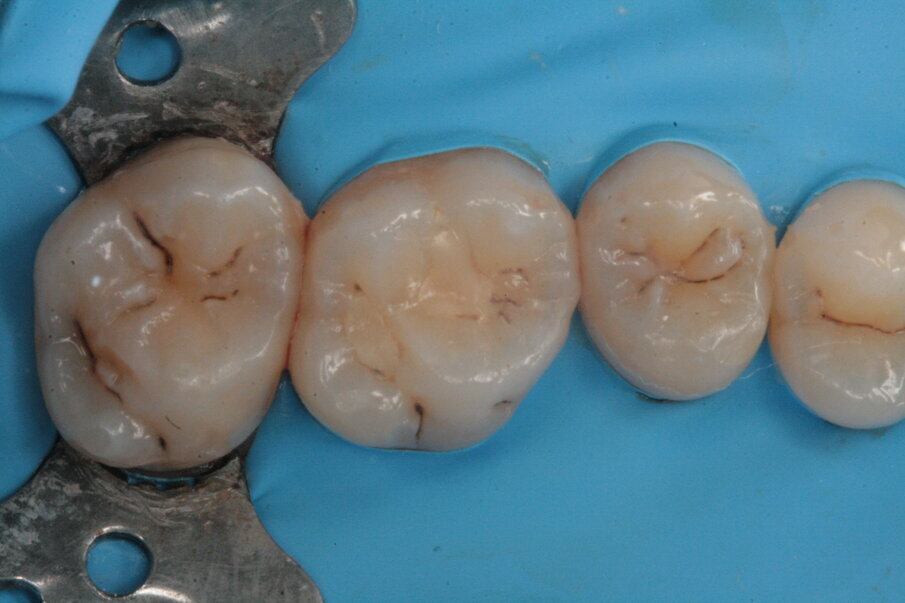

Gli elementi da trattare erano il 27, 26, 25 e 24 (Figg. 12-14); esattamente come per il settore 1, alcune lesioni cariose si approfondivano in dentina mentre altre (24, 25) rimanevano confinate allo smalto permettendo cosi una cura precoce della patologia e l’esecuzione di un’odontoiatria minimamente invasiva per preservare al meglio il tessuto smalteo (Figg. 13-18).

Figg. 15, 16_Preparazione delle cavità.